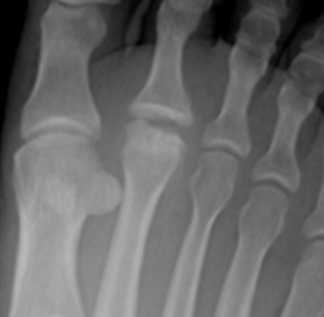

- Болезнь КеллераII. На снимках выявляются патологические изменения в головке пораженной плюсневой кости. В зависимости от срока заболевания может обнаруживаться остеопороз, уплотнение и деформация головки плюсневой кости, ее патологический перелом и дефрагментация.

Формализованный протокол. СТОПА (схема). Болезнь Келера 2.

Определяется деформация и уплощение головки 2, 3, 4 плюсневой кости. На фоне разряжения структуры костной ткани головки дифференцируются плотные островки с четкими, неровными контурами. Дистальный метафиз 2 плюсневой кости несколько утолщен, по всей видимости, за счет периостальных наслоений. Суставная щель во 2 плюсне - фаланговом суставе расширена.

Суставные поверхности, образующие плюсне-фаланговый сустав, инконгруэнтны, форма суставных поверхностей деформирована, уплощена, склерозирована в области . Величина суставных поверхностей увеличена за счет краевых костных разрастаний. Контуры замыкательных пластинок эпифизов ровные, чёткие. Подхрящевой (субхондральный) остеосклероз, как свидетельство функциональной несостоятельности суставных хрящей и свидетельствующий о перегрузке костной ткани, определяется в области . По краям суставных поверхностей определяются костные разрастания (свидетельствуют о функциональной несостоятельности суставных хрящей).

ДИАГНОСТИЧЕСКОЕ ЗАКЛЮЧЕНИЕ:

Остеохондропатия головки 2 плюсневой кости - болезнь Келера 2 правой стопы, картина деформирующего артроза 2 плюсне-фалангового сустава 2 (второй) стадии по классификации Н.С. Косинской.